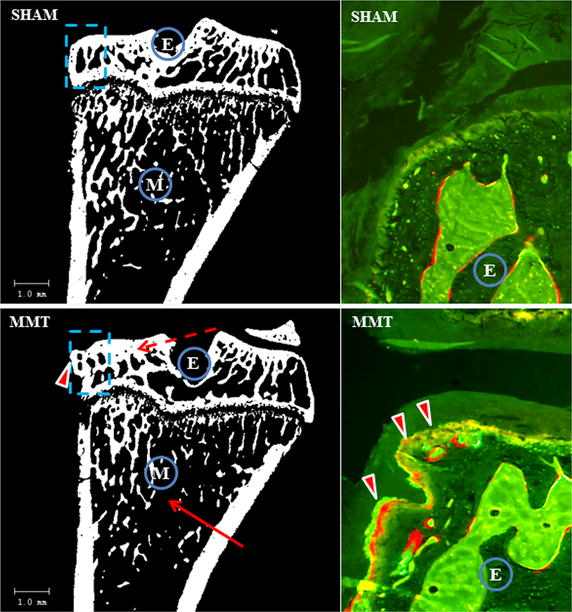

Two-dimensional µCT image of the proximal tibia from sham and MMT rat. Cortical and cancellous bone was measured for the entire epiphysis (E), whereas cancellous bone was evaluated at the metaphysis in the area of secondary spongiosa (M). Solid arrow indicates a lesser amount of cancellous bone in MMT rat; dotted arrow indicates thickening of the subchondral bone in MMT rat; arrowhead indicate osteophyte formation in MMT rat. Dotted blue square indicates area of epiphysis where UV micrographs are taken to show the new bone formation. Arrowheads indicate intensive bone remodeling of the osteophyte in MMT rat as judged by the presence of both calcein and alizarin red dye, whereas there is no osteophyte formation in the sham rat

Dynamic histology revealed active bone remodeling and active osteophyte formation at the medial epiphysis of the MMT rats compared to the sham rats, whereas at the tibial metaphysis, the sham rats exhibited more bone formation and more cancellous bone than the MMT rats (Fig. 2).